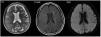

La primera prueba aconsejada, tras una exploración neurológica detallada, generalmente es el TC cerebral sin contraste, en el cual se puede observar edema cerebral y realce cortical de las áreas afectas o del espacio subaracnoideo22, aunque también puede haber ausencia de signos radiológicos20. Especialmente el TC dual energy permite diferenciar si las hiperdensidades observadas corresponden a contraste o hemorragia12. Los casos reportados de pacientes en HD no presentan signos radiológicos distintos (fig. 1). Otra prueba útil es la RM por su capacidad de evidenciar lesiones isquémicas, principalmente con la secuencia DWI mediante la restricción en la difusión producida por la isquemia; la secuencia FLAIR identifica las áreas edematizadas22 (fig. 2). Otro examen que ayuda a la diferenciación, especialmente respecto la hemorragia subaracnoidea, es el análisis del líquido cefalorraquídeo (LCR), donde la ausencia de xantocromía o hematíes iría en contra de esta, así como una concentración de contraste superior a la sanguínea iría de la mano de la extravasación del mismo4.

Tomografía computarizada (TC) cerebral sin contraste de mujer de 63 en hemodiálisis sometida a tercera embolización endovascular de aneurisma de la arteria comunicante anterior íntegro con hemiparesia izquierda posprocedimiento (sometida a dos intervenciones previas sin incidencias en el pasado). TC muestra hiperdensidad cortical en el surco de ambos lóbulos frontales. Matsubara et al.3 Con permiso de los autores.